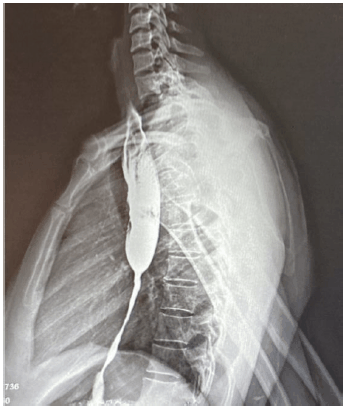

Paciente sexo feminino, 40 anos, procura atendimento com quadro de disfagia progressiva, no momento para líquidos, dois anos após ingesta de soda cáustica. Submetida à esofagografia, como mostra a imagem a seguir.

Enunciado 3137035-1

Em relação ao caso, assinale a melhor conduta endoscópica.